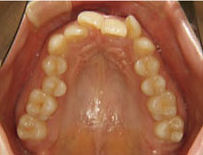

上顎

治療後

前歯のガタガタもなくなり、きれいにそろいました。

主訴:ガタガタが気になる

所見:犬歯の低位唇側転位、叢生

治療方法:上下非抜歯、歯列拡大

治療内容:マルチブラケット装置による非抜歯治療